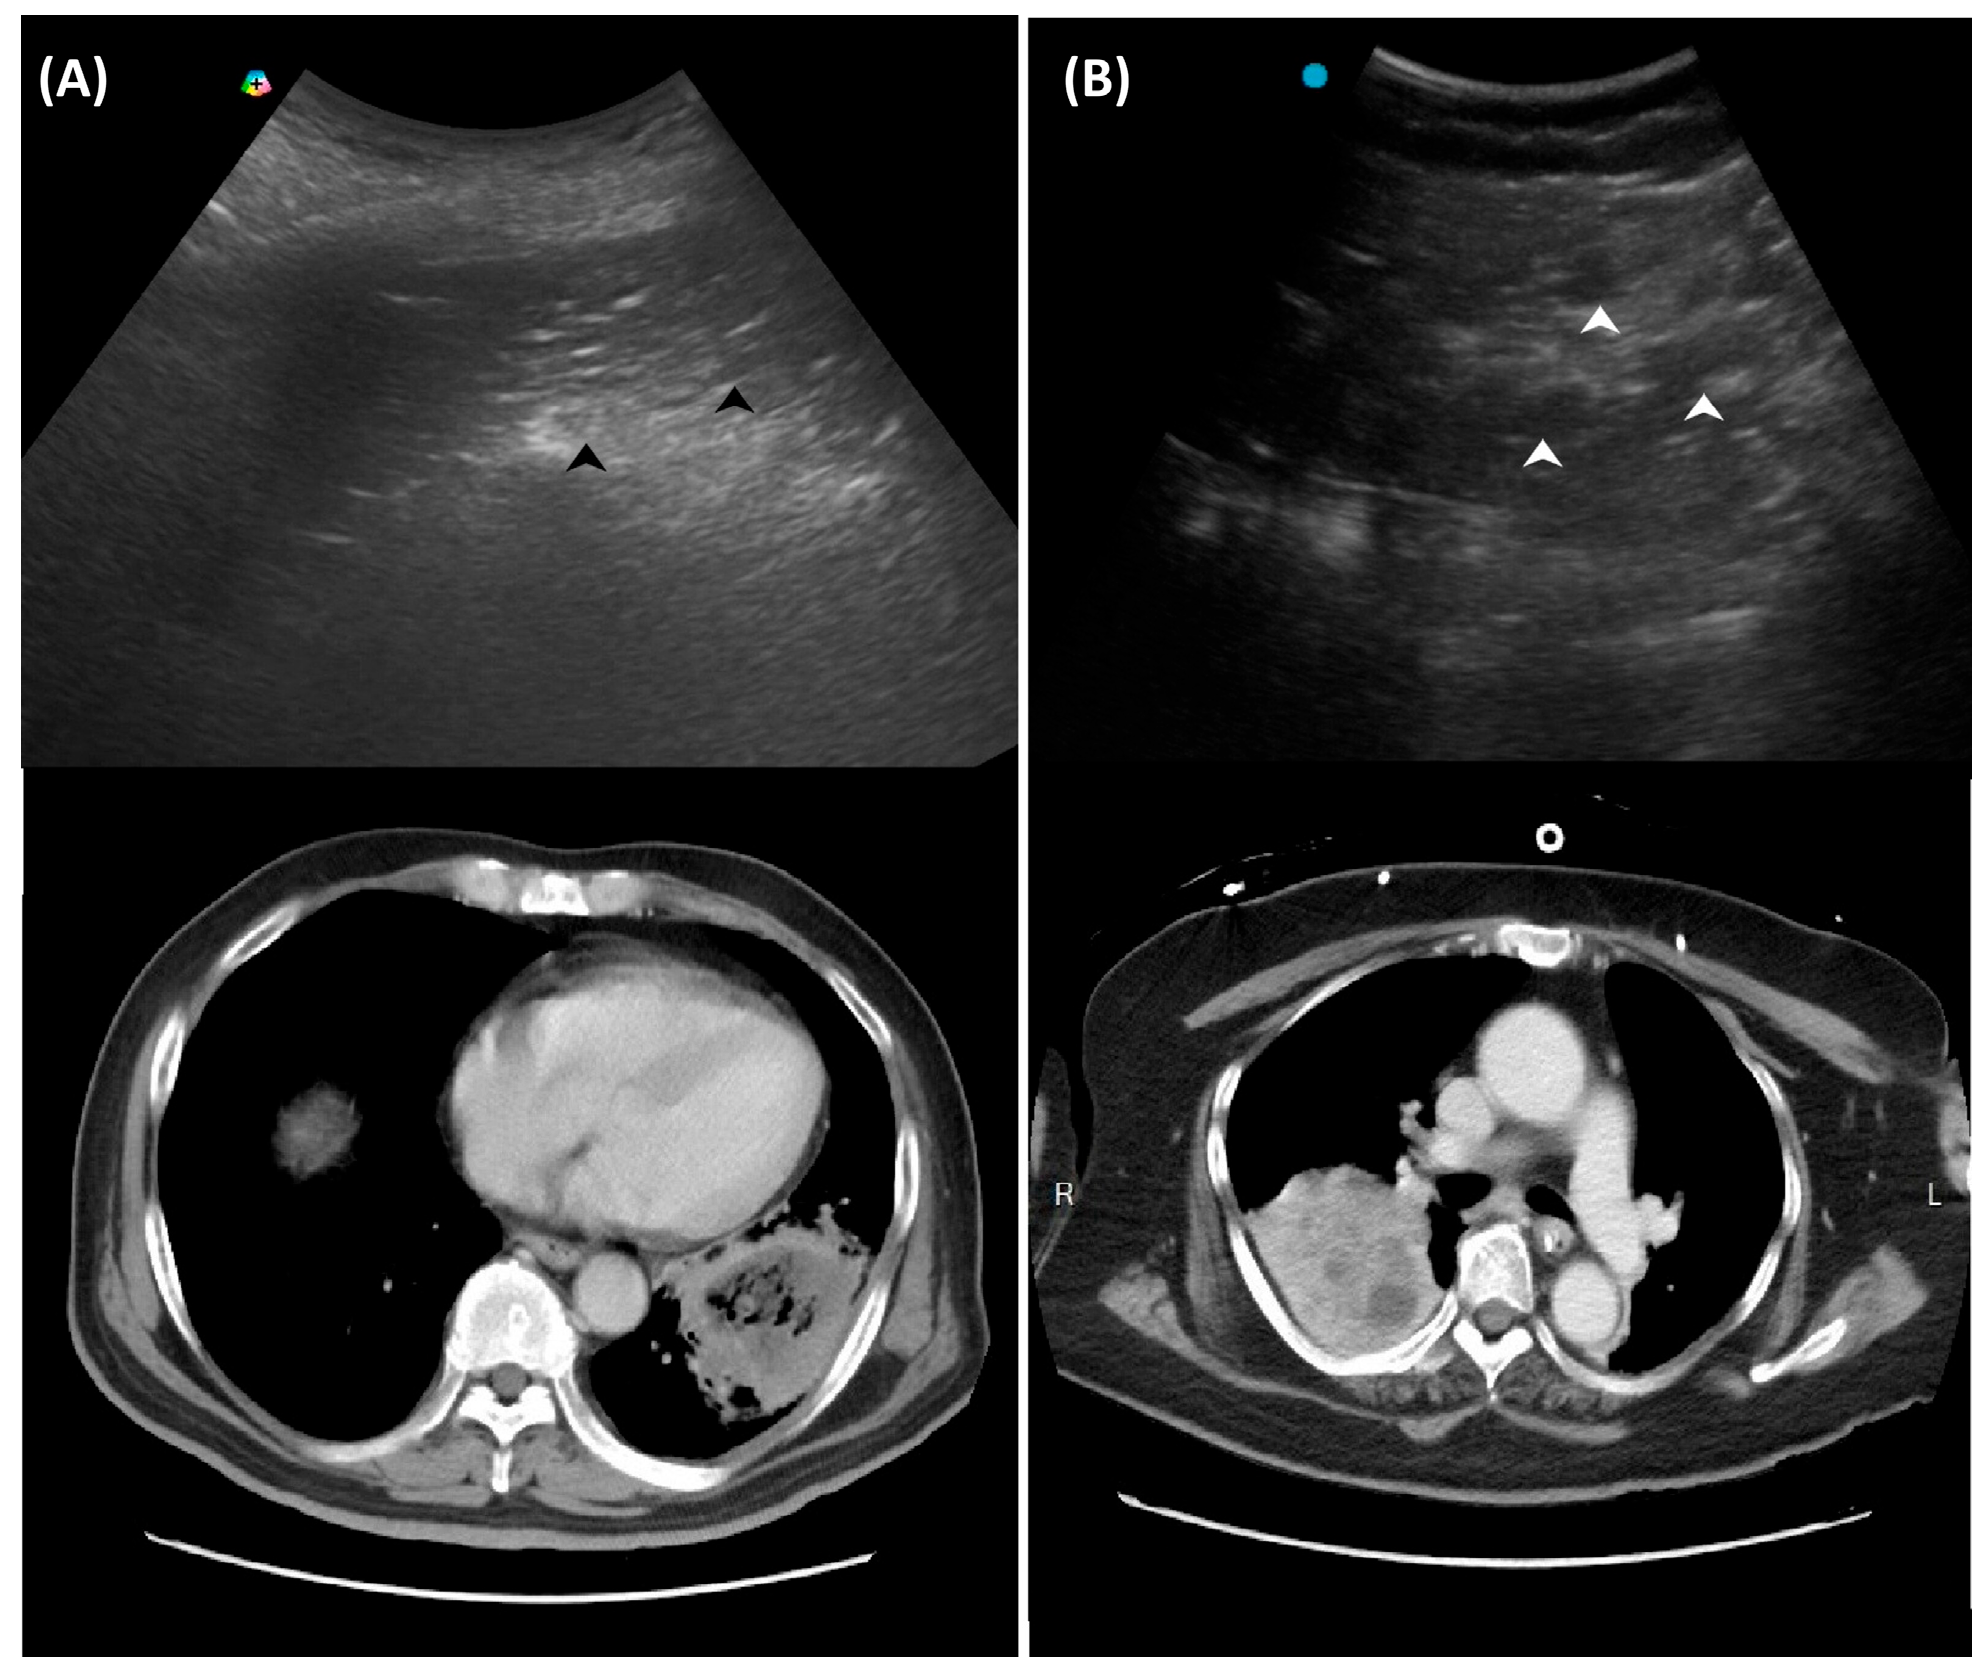

| Absence of color Doppler signals within consolidation (poor perfusion) | Necrotizing pneumonia |

| Hypoechoic lesions or microabscesses within consolidations | Necrotizing pneumonia |